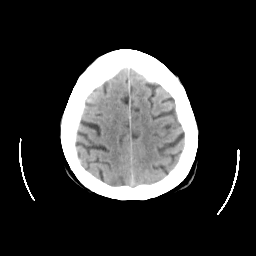

CT Study #2 -- Slice #23